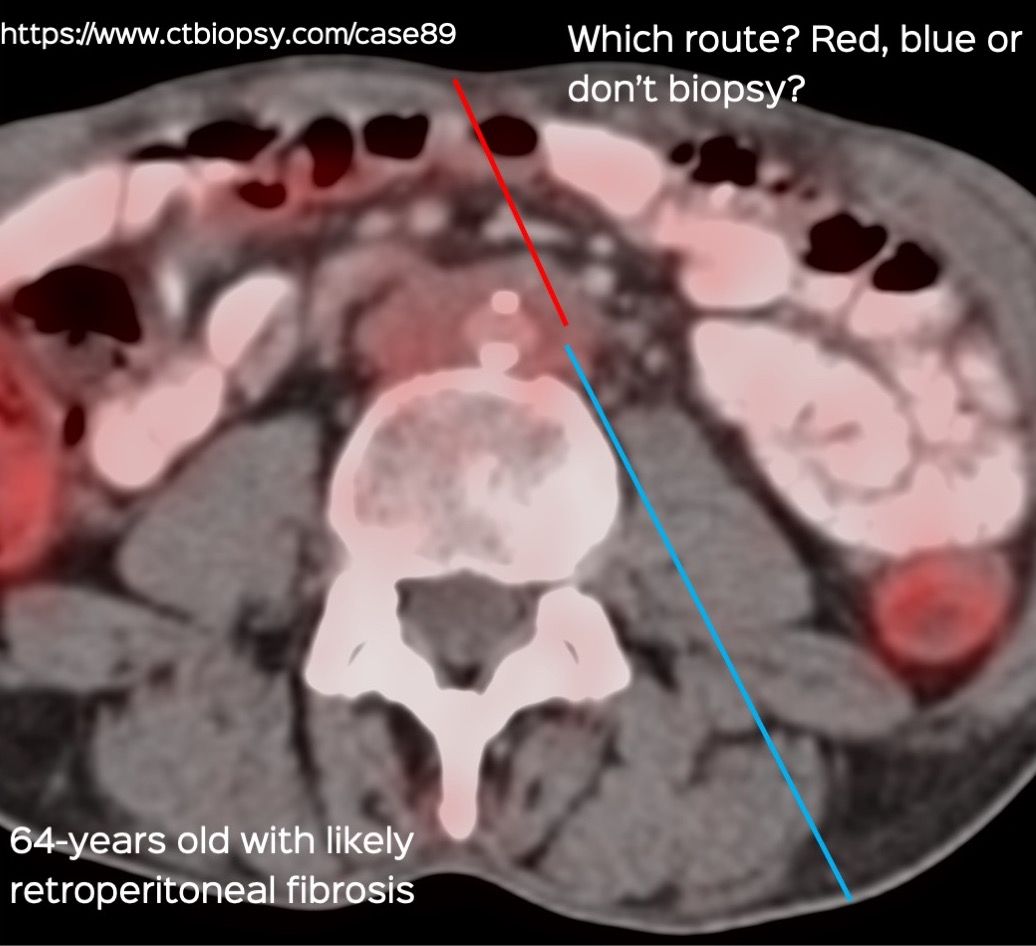

Case 170 - Peri-Aortic Soft Tissue Biopsy

Bhavin Jankharia - 23 August 2025